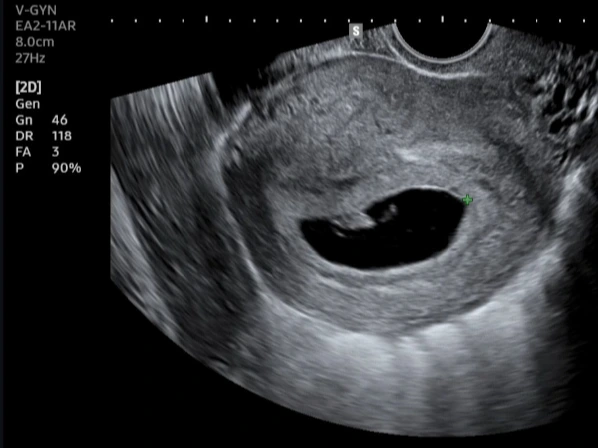

아이가 생긴 것을 눈으로 확인한 임신 7주 차 초음파 검사결과; 사진 가운데 검정 고구마 형태를 띤 부분이 태낭이라고 불리는 '아기집'이고, 그 상단에 초보 형태의 태아가 보인다.